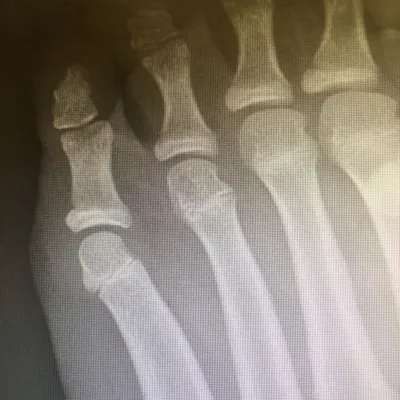

Examples of Pediatric Foot Fractures (Below)

Pediatric Coalition Fracture of the DIPJ fifth toe initial and healed